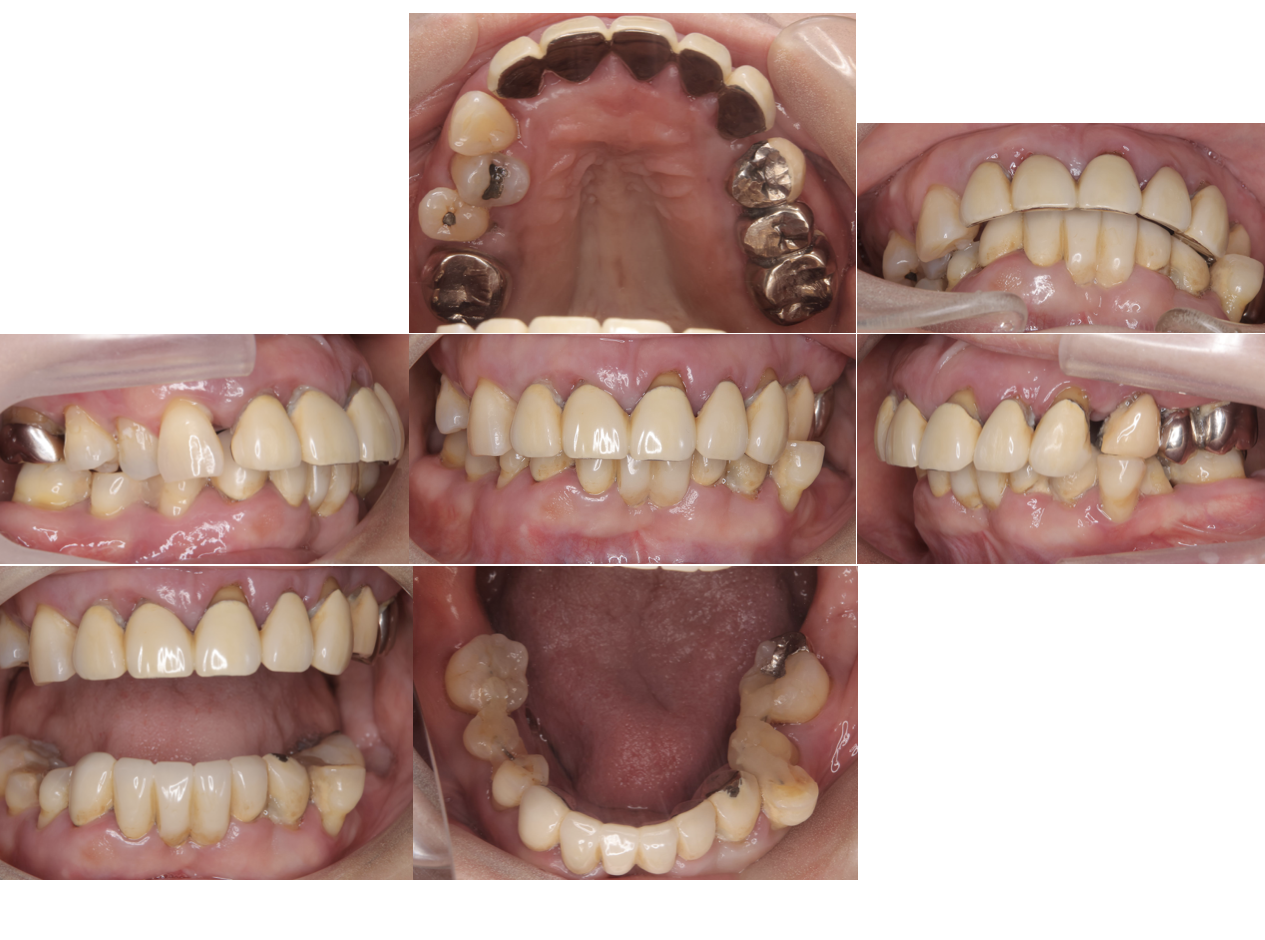

参考例

初診時の口腔内写真

当院でもこのような術前の写真を撮影し、個々の歯の虫歯、歯周病の状態、お口の全体の、歯並び、噛み合わせの状態などについてもご説明しております。写真を使って、目で実際に見ることで、話で説明を聞くだけよりも理解力が上がり、自身の歯やお口のことについて理解が深まりやすいと思います!

またこのように、治療中の写真なども撮影しながらより自分の歯がどういう状態からどういう状態になったのかを目で見て理解していただきながら治療を受けていただくことでより安心して通院していただけると思っています。